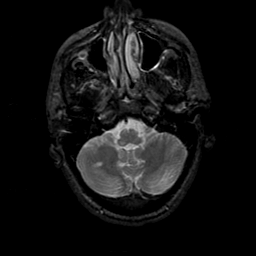

MR Study #23, January 26, 1992 -- Slice #9